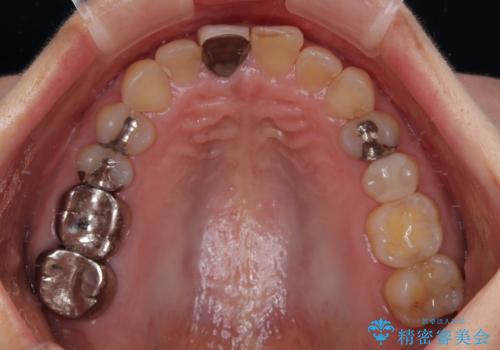

- 保険診療で装着した前歯のクラウンが変色して気になってきたとのことで来院された患者様です。

歯肉退縮による歯肉ラインの黒い縁も気になってきたとのことで、オールセラミッククラウンにて補綴治療を行うこととしました。